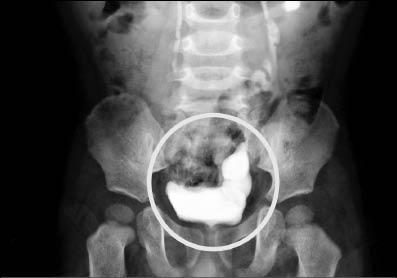

高長震波碎石護理師高儷芳說,小病人體外震波碎石,需要很小心,怕他亂動,得全身麻醉。也因為年紀小,結石形成時間不久、硬度不大,經體外震波擊中後,呈粉碎剝落,隔天X光檢查,石頭碎片隨著輸尿管順利排出。